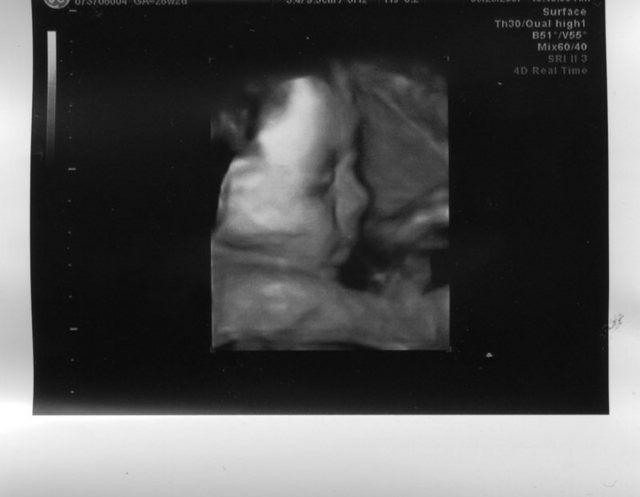

The last time we saw him, he looked like this;